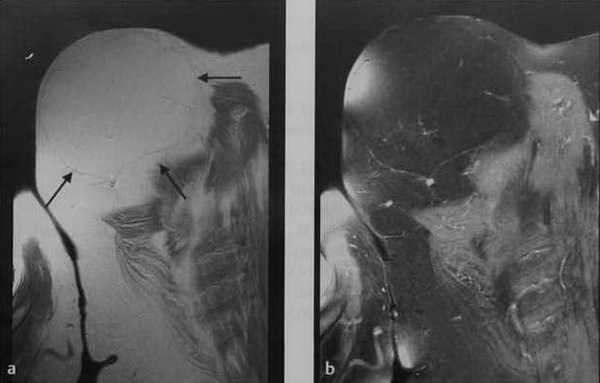

а,b Женщина 75 лет с крупной подкожной липомой на задней поверхности плеча: а) Фронтальная плоскость, Т1 -взвешенное изображение. Крупное образование с перегородкой, изоинтенсивное жировой ткани; b) Постконтрастное Т1 -взвешенное изображение с подавлением МР-сигнала от жировой ткани. Отсутствие накопления контрастного вещества опухолью и ее перегородками, что исключает миосаркому.